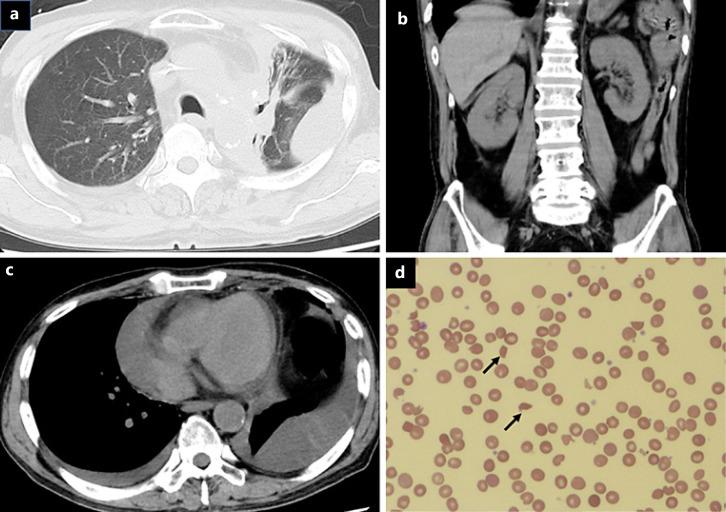

A 69-year-old man with refractory lung adenocarcinoma was treated with gemcitabine and vinorelbine. Dyspnea and hypertension developed after the 17th cycle of chemotherapy. Laboratory findings revealed intravascular hemolysis and renal dysfunction. Thrombotic microangiopathy (TMA) was confirmed by renal biopsy. Antihypertensive and steroid therapies were ineffective. After plasmapheresis, intravascular hemolysis and renal dysfunction gradually improved. However, the disease progressed, and he died 6 months after TMA diagnosis. Autopsy revealed similar pathological findings to those of the renal biopsy. It is important to discontinue gemcitabine at the onset of TMA and consider TMA when using gemcitabine for long periods.

一名69岁的难治性肺腺癌男性患者接受了吉西他滨和长春瑞滨治疗。在第17周期化疗后出现呼吸困难和高血压。实验室检查发现血管内溶血和肾功能不全。肾活检确诊为血栓性微血管病(TMA)。抗高血压和类固醇治疗无效。血浆置换后,血管内溶血和肾功能不全逐渐改善。然而,疾病进展,他在TMA诊断后6个月死亡。尸检显示与肾活检相似的病理结果。在TMA发作时停用吉西他滨并在长期使用吉西他滨时考虑TMA很重要。